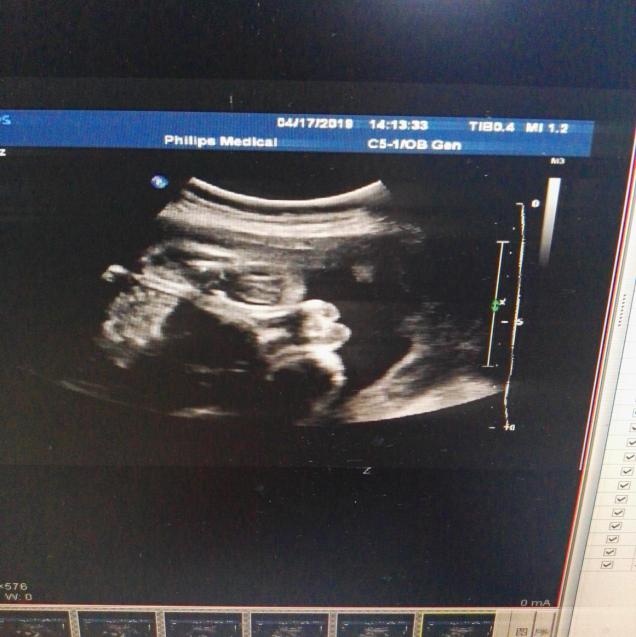

F2胎儿超声测值:

双顶径 75mm,头围 289mm,腹围243mm,股骨长 54mm,最大羊水深度 53mm,羊水内见一条带样高回声漂浮。

胎心率 156次/分,胎盘位于后壁,厚约31mm。

阳性指征:探查时胎儿外生殖器呈“郁金香”征。

超声提示:胎儿外生殖器呈“郁金香”征(待排),建议复查